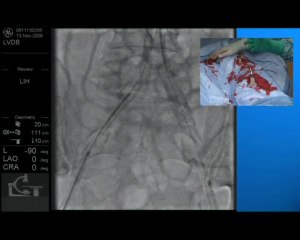

Dr. Rob Williams (Interventional Radiologist) demonstrating how to stent the external iliac artery using a Simbionix simulator.